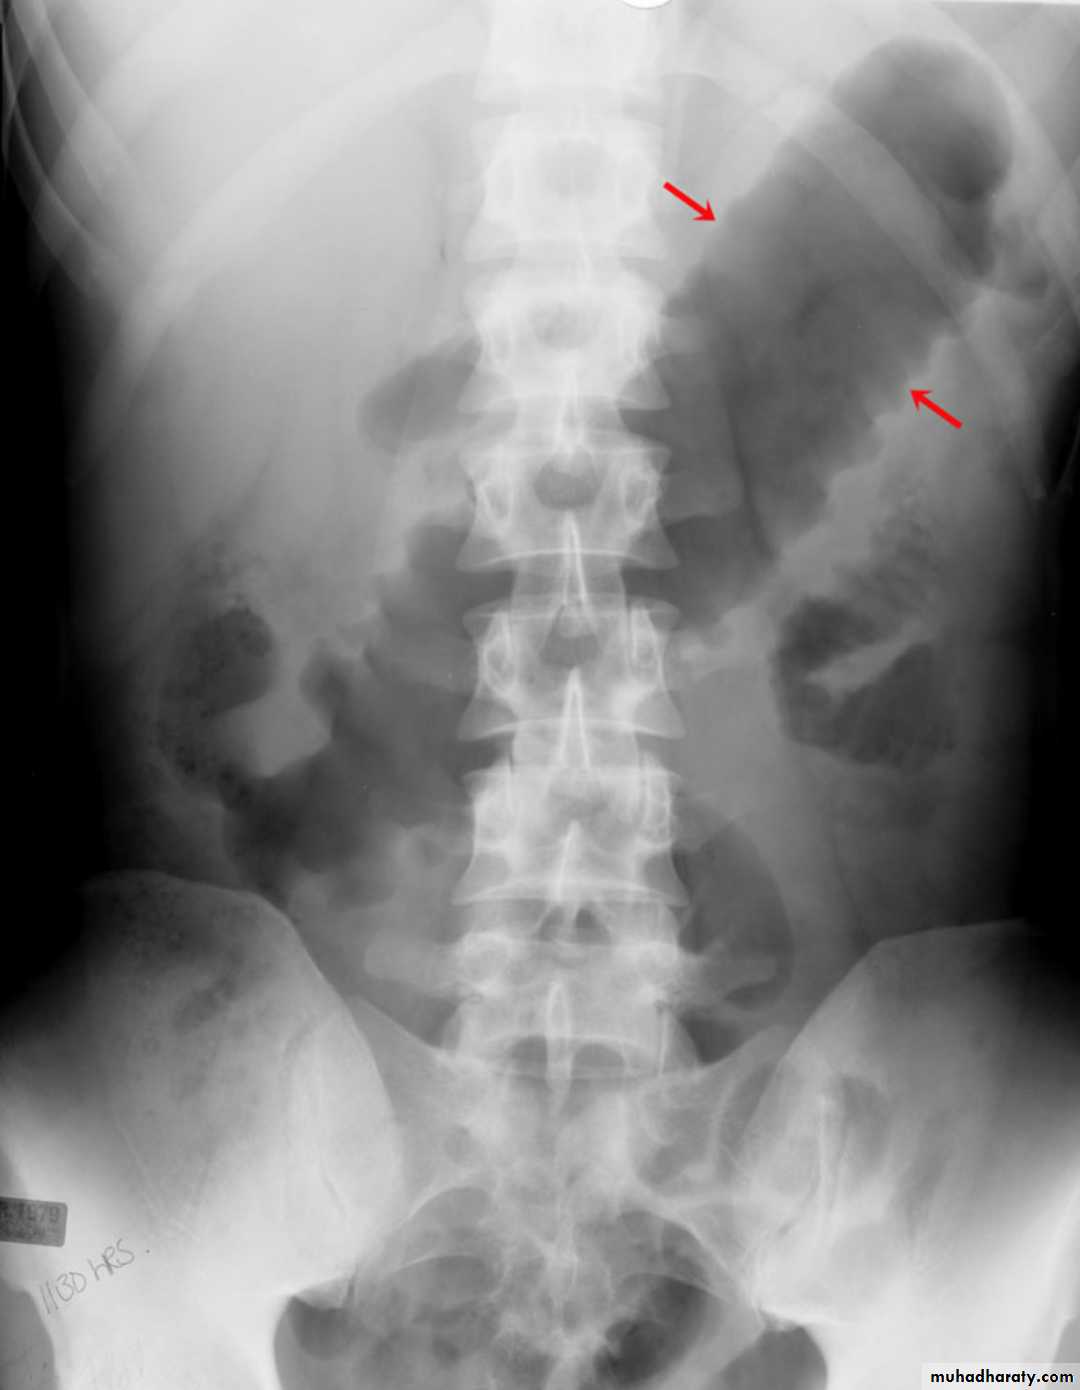

toxic megacolon (TM) is complication that can be seen in both types of inflammatory bowel disease more in UC , in infectious colitis, as well as in some other types of colitis.

Radiographic features OF TOXIC MEGACOLON

The colon (typically transverse colon) becomes dilated to at least 6 cm (usually greater). There is additional loss of haustral markingsIt is serious acute abdominal condition

More in UC > CD